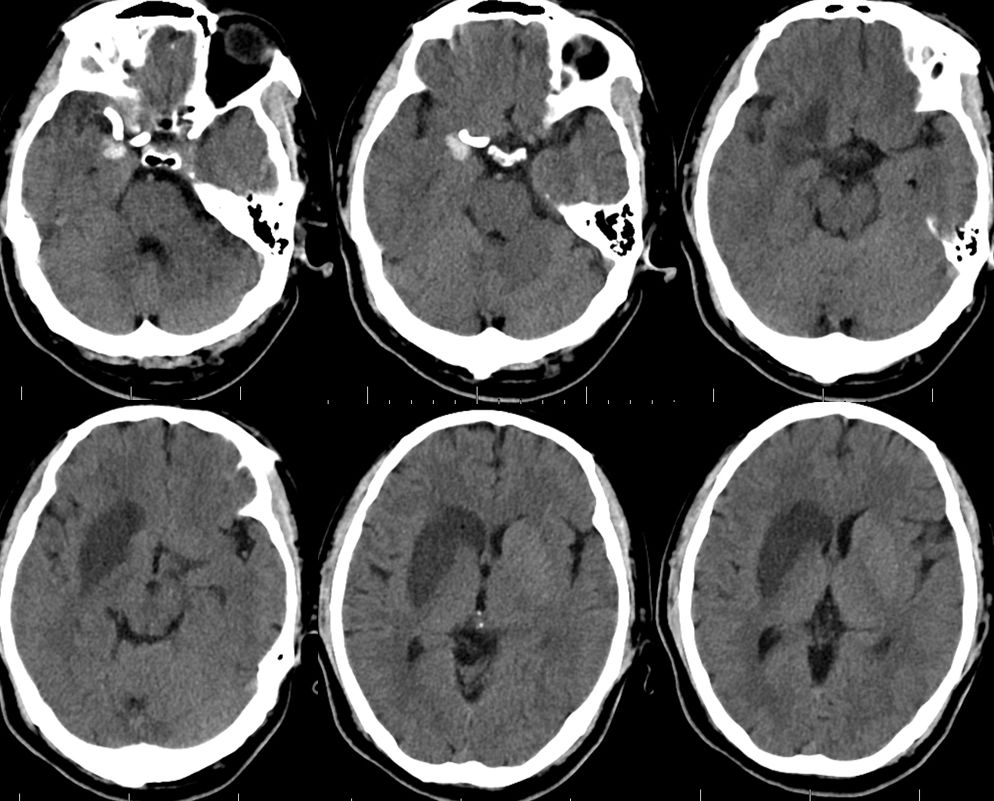

1、术后18小时CT(图五)。

图五

术后3天CT(图八)。

图八